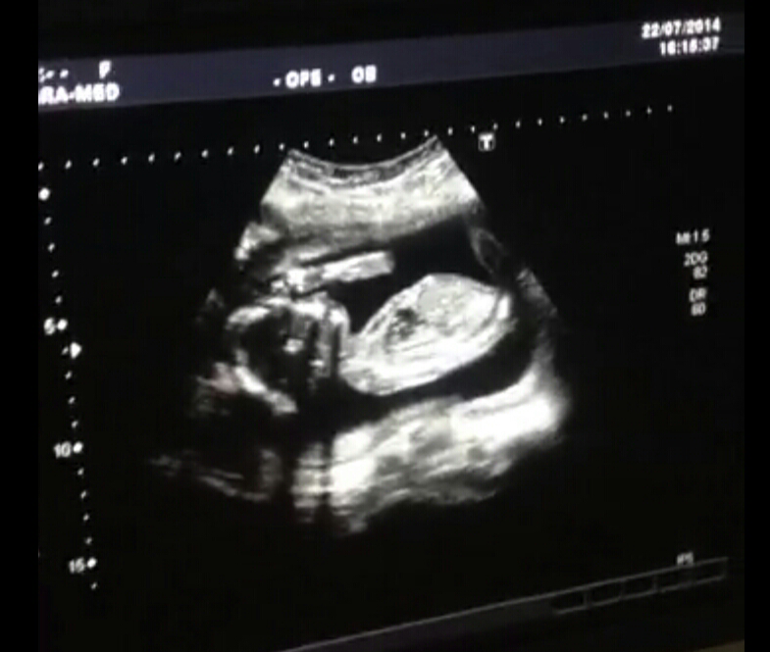

Испугалась что малыш не шевелится полтора дня... вчера перенервничала но врач сказала что ребенок очень активный))))) фото под катом

Все хорошо с ним) лежал икал, пузыри пускал) нам распечатали 5 фото) все показали) сказали что плод большой весь в папу

Ручкой за носик хватался) и ножки показали)

Поздравляю!! :) Я всегда думала, что снимки УЗИ у всех одинаковые, но смотрю на ваши фотографии, все-таки нет, видно очертания личика) У нас носик другой и губки) прикольно)